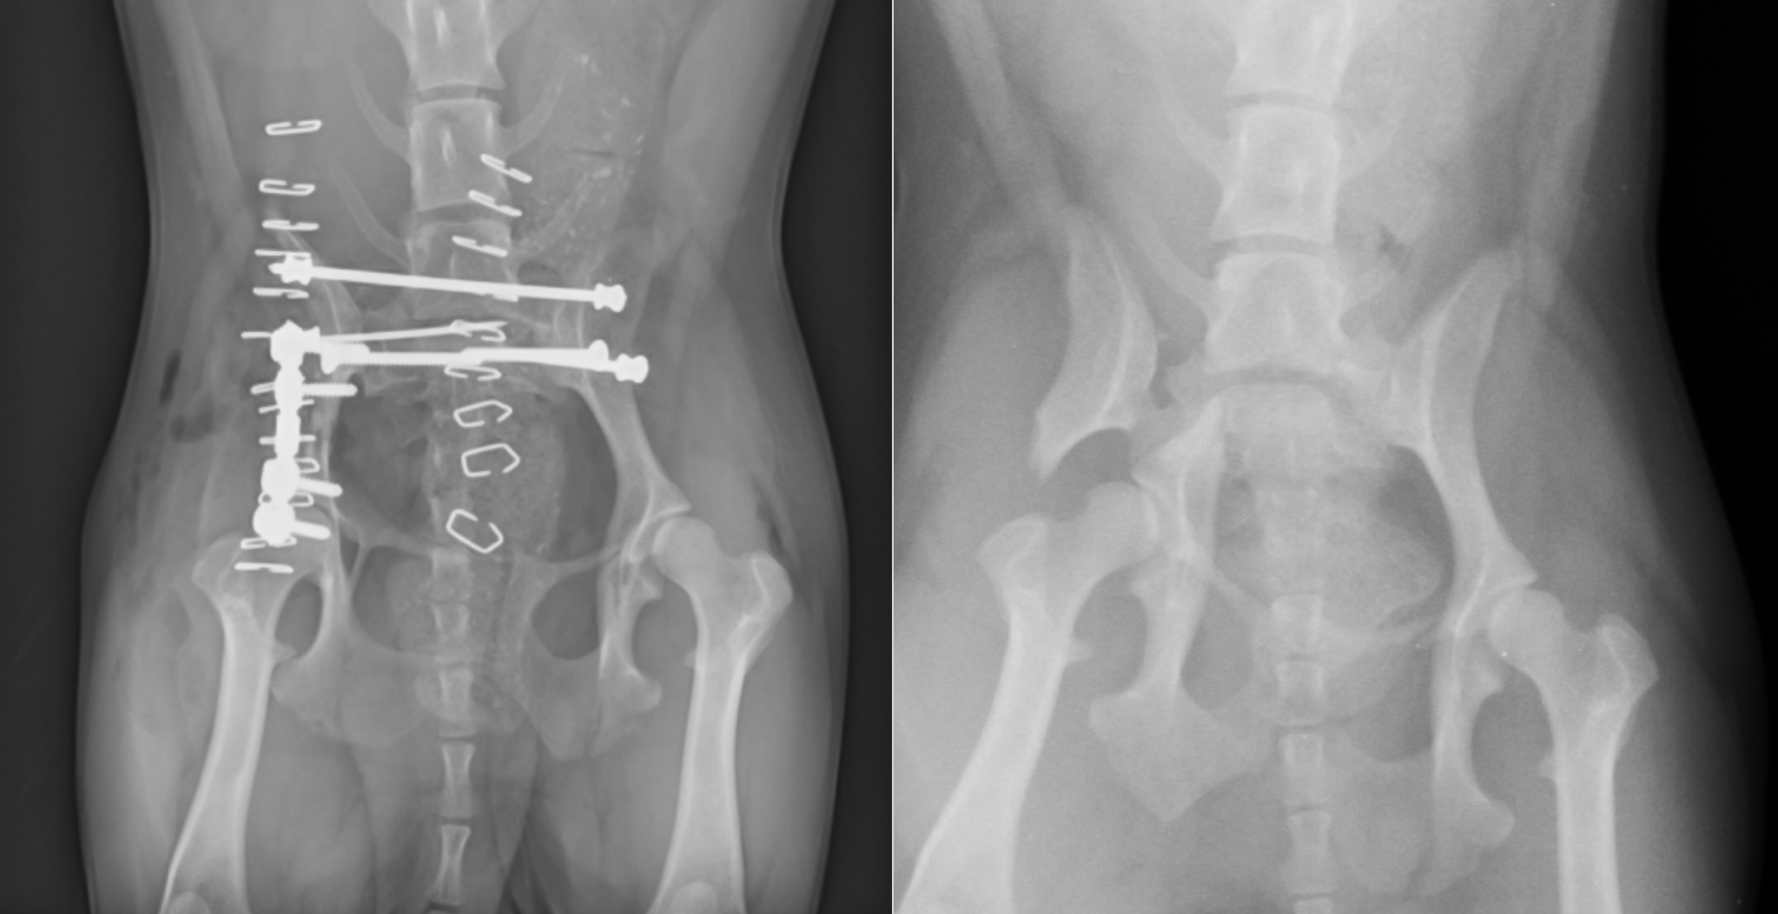

チワワの症例です。左右の仙腸関節が脱臼(正確には左は仙骨骨折)しています。緑は左の仙骨骨折、赤は右の仙腸関節脱臼、黄色は右の腸骨骨折をさしています。

仙腸関節脱臼と、仙骨骨折はボルトとアンチローテーションピンで止めてあるのと、腸骨翼にロングボルトというものを入れて狭窄を予防しています。また、右の腸骨の骨折にはパールプレートと呼ばれるプレートを入れて固定しています。